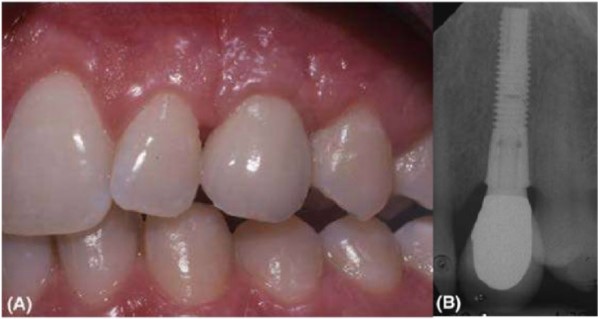

(A) Răng cửa bên hàm trên được thay thế bởi một implant cho thấy hình dạng mô mềm tốt và thẩm mỹ. (B) Hình ảnh X quang của implant, trường hợp này đường kính nhỏ khoảng 3.3 mm Nobel Biocare. Implant đường kính nhỏ thích hợp cho vị trí chịu lực ít.